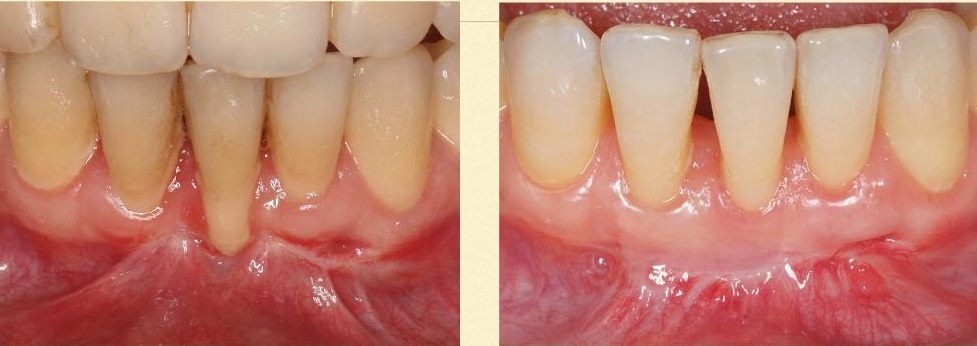

Пластика преддверия с пересадкой свободного десневого аутотрансплантата с неба для лечения рецессии десны у резца, и профилактики дальнейшего ухудшения состояния пародонта зубов